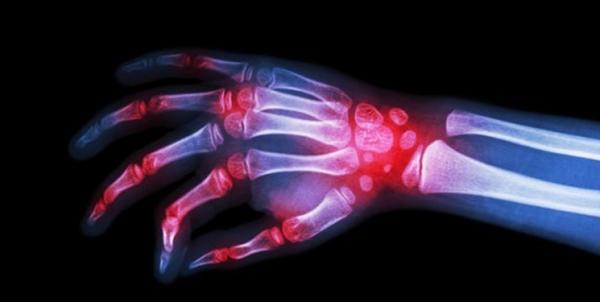

به گزارش فارس، داروی آزمایشی جدید درمان بیماری رماتیسم مفصلی نتایج امیدبخشی را در فاز نهایی آزمایشات بالینی انسانی نشان داد. این دارو که نسخه جدیدی از داروی «JAK-inhibitors» است مورد تایید سازمان غذا و داروی آمریکا قرار گرفت و امید است این دارو طی ۱۲ ماه آینده به تولید برسد.

براساس گزارش «نیواطلس»، این دارو شامل چهار مولکول مرتبط با یکدیگر به نامهای JAK1، JAK2، JAK3 و TYK2 است که هرکدام از آنها نقش اساسی در تسهیل سیگنالهای التهابی سلولی ایفا میکنند.

طبق این گزارش، در سالهای ۲۰۱۱ تا ۲۰۱۲، دو داروی JAK inhibitors ابتدایی وارد بازار شد. نسل اول این داروها تا حدودی موثر بود اما به دلیل نداشتن برخی ویژگیها، باعث ایجاد عوارض جانبی مختلفی در بیمار میشدند. اکنون نسخه جدید JAK inhibitors که به مرحله پایانی آزمایشات انسانی رسیده است، به گونهای طراحی شده که با دقت بیشتری مولکولهای JAK را مهار میکند و امید است که با عوارض جانبی کمتری موثر واقع شود.